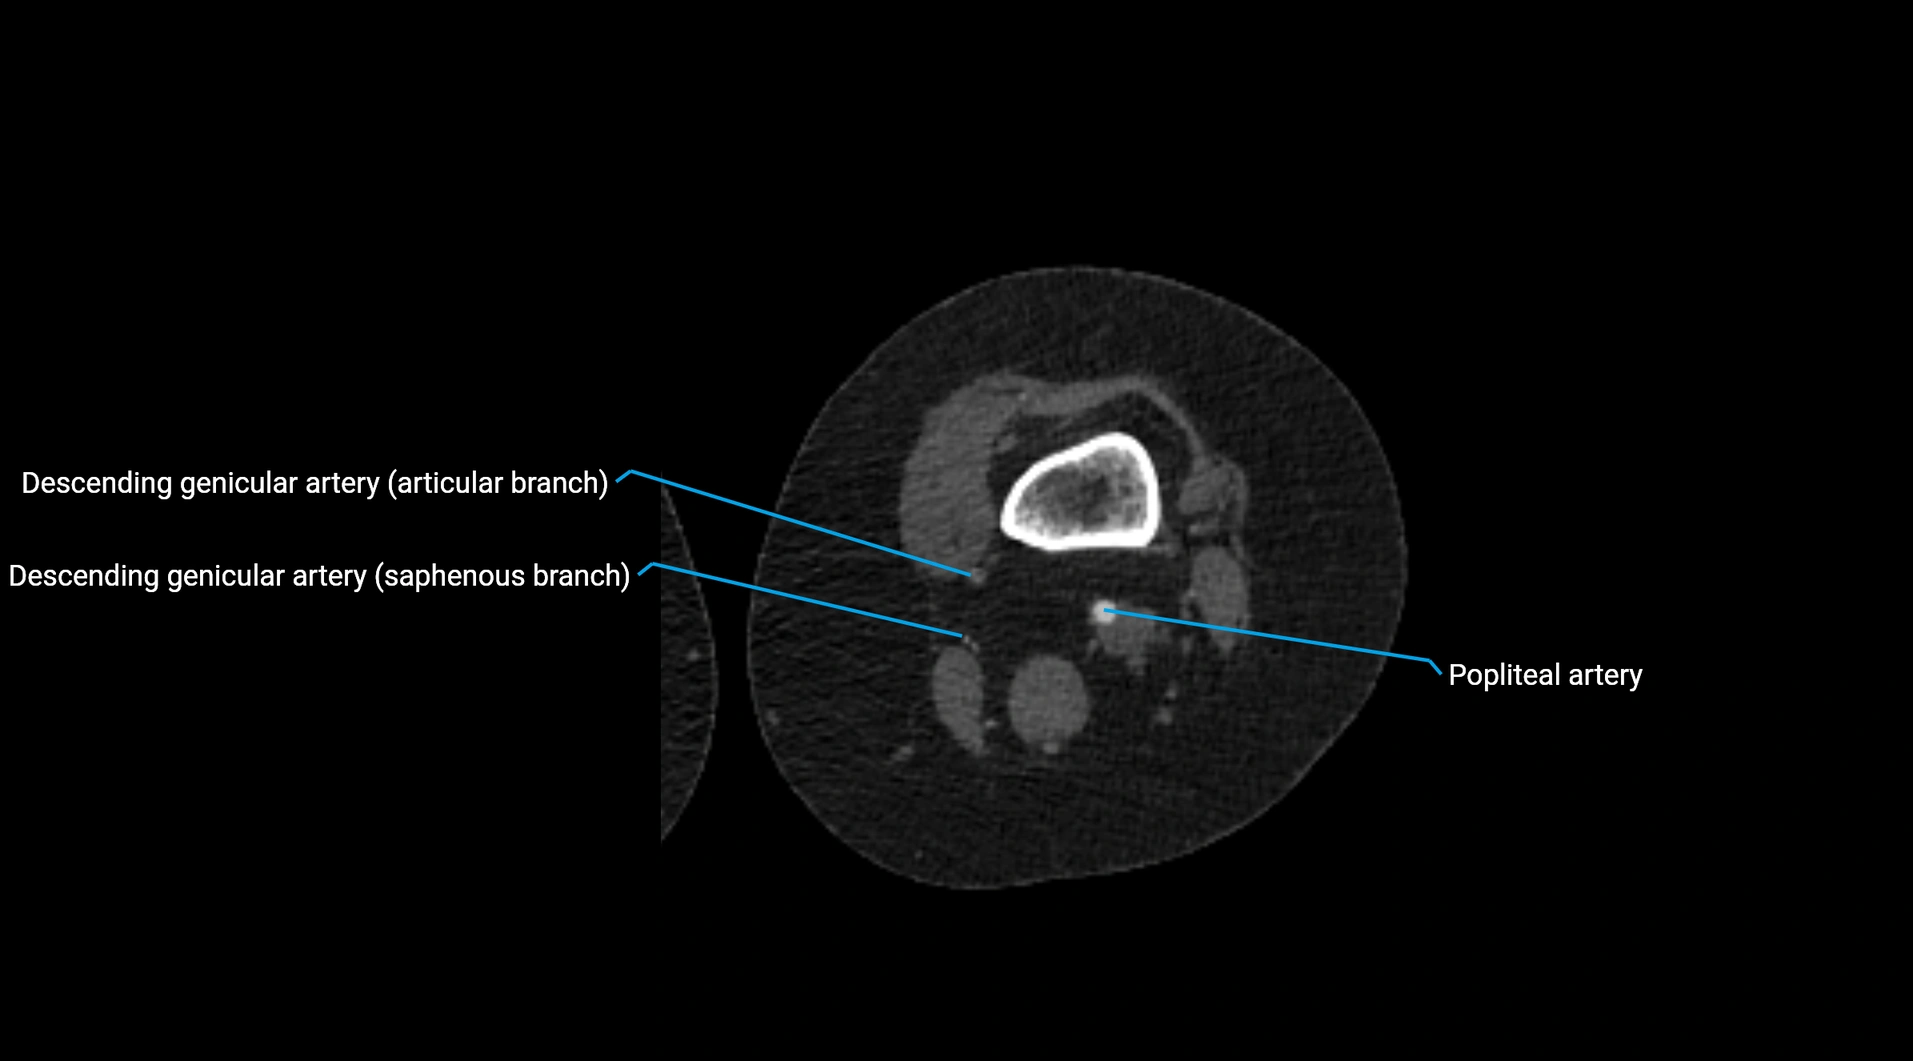

CT Appearance

Contrast-enhanced CT (CTA):

• Gold standard for abdominal aortic imaging

• Provides excellent detail of lumen, wall, aneurysm, thrombus, and branch vessels

• Multiplanar and 3D reconstructions help in aneurysm measurement, stent graft planning, and dissection evaluation

• Detects acute rupture, traumatic injury, or occlusion with high sensitivity